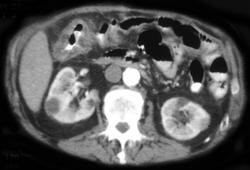

Pseudomembranous Colitis (PMC)